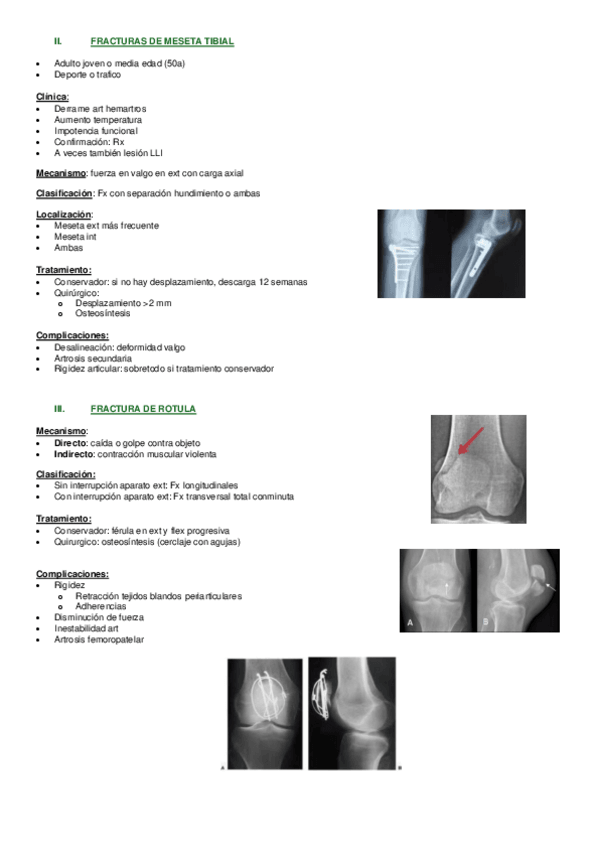

He publicado nuevos apuntes de 2º Fisioterapia en Especialidades Clínicas I: 26.-F-en-patologia-traumatica-de-rodilla.pdf